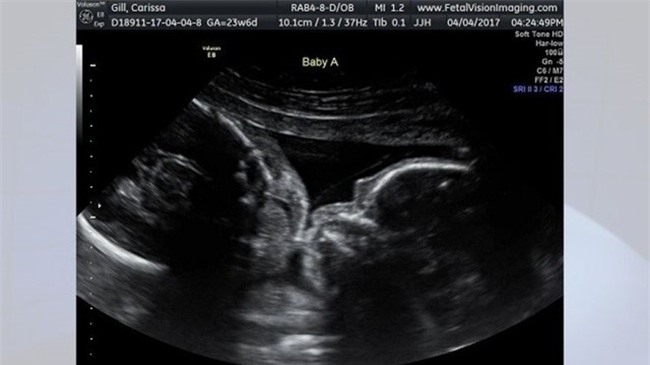

tại Levittown cùng bạn trai Randy. Cả hai người vô cùng bất ngờ khi hình

ảnh siêu âm cho thấy hai thai nhi đang trong tư thế quay đầu vào nhau

và gần như môi chạm môi.

Carissa Gill chia sẻ hình ảnh thai nhi trong lần siêu âm gần nhất tại phòng khám thai Vision Imaging. Ảnh: Carissa Gill.